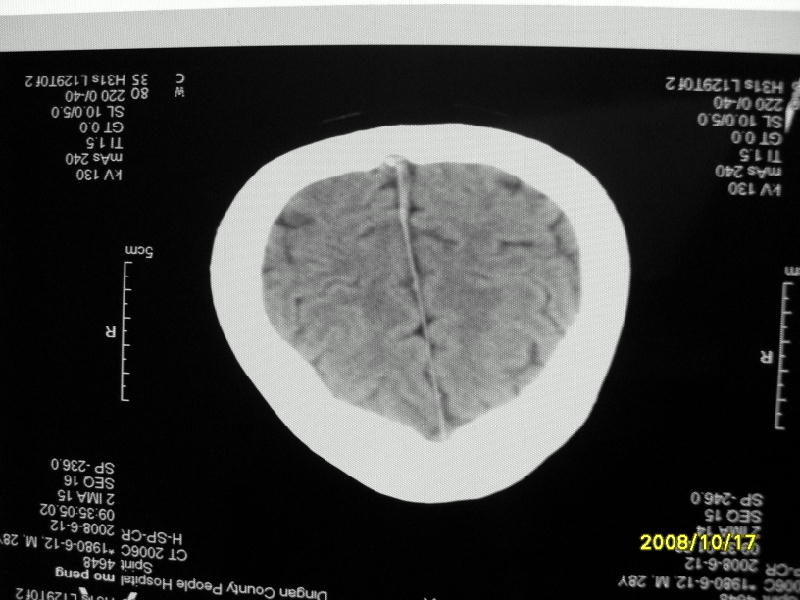

检查名称:     ct颅脑平扫           男     28岁

表现:左顶叶见斑点状致密影。边缘清,大小约0。3*1。0cm,余脑实质密度及灰白质结构示见异常。脑室系统大小,形态,密度未见异常。脑沟。脑裂。脑池未见异常密度影。中线结构无移位。

印象:左顶叶少许钙化灶

左顶叶见斑点状致密影。边缘清,大小约0。3*1。0cm,余脑实质密度及灰白质结构示见异常。脑室系统大小,形态,密度未见异常。脑沟。脑裂。脑池未见异常密度影。中线结构无移位。

印象:左顶叶少许钙化灶。